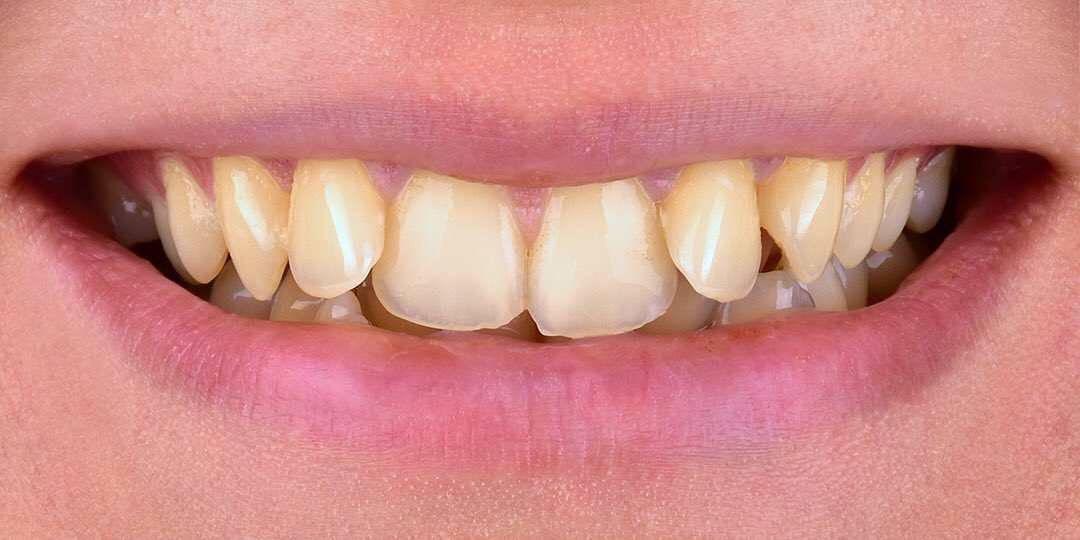

Diş Beyazlatma

Dişlerin yapısal olarak kendine has bir rengi vardır. Yenilen yemekler, sigara, çay, kahve, kola, şarap, vişne vs gibi etmenler dişlerde...

Bleaching

Devamını Oku